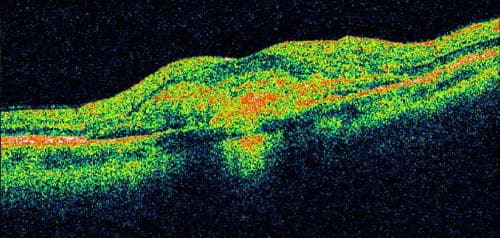

Optical Coherence Tomography(OCT)is also an important test in assessing AMD, both in diagnosis and response to treatment. OCT can reveal microscopic changes in the architecture of the macula, including retinal swelling, fluid and atrophy that often cannot be detected during a clinical exam.

OCT Image Showing Wet AMD